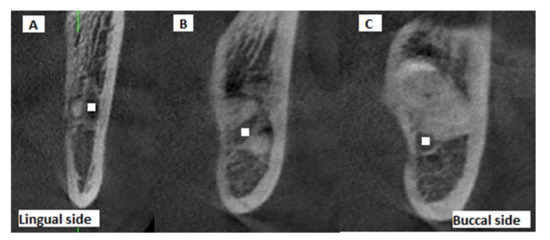

Moreover, the position of the MC relative to the root apex of the IMTM (lingual, inter-radicular or buccal position) was determined on the CBCT scans and recorded (Figure 3). The presence/absence of contact between the MC and the IMTM root was also evaluated on coronal, axial, and cross-sectional CBCT views and recorded.

Figure 3. Cross-sectional CBCT views showing the buccolingual position of the IMTM apex relative to the MC: (A) buccal, (B) inter-radicular, (C) lingual (white squares: center of mandibular canal).